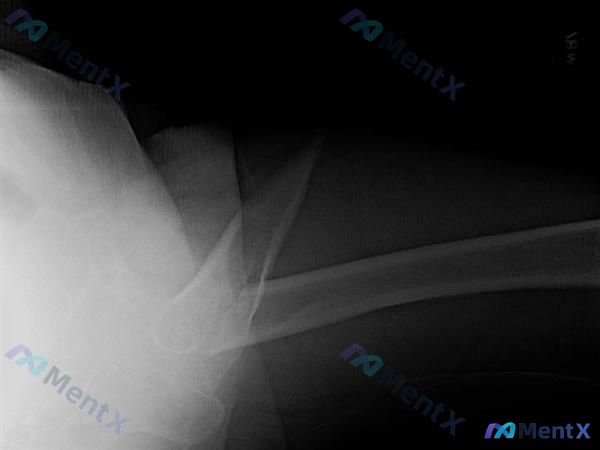

整理到一个病例,觉得术中复位这块的逻辑挺典型的,还有个容易带偏思路的病史点,放出来讨论下。 病例基础信息 - 66岁男性,有前列腺癌史 - 园艺时从山上摔下 影像初步结论 - 左侧股骨转子间骨折,伴明显移位 - 肱骨近端复杂性骨折(粉碎性考虑) - 盆腔可见多枚金属内固定物(既往手术史) - 局部骨...